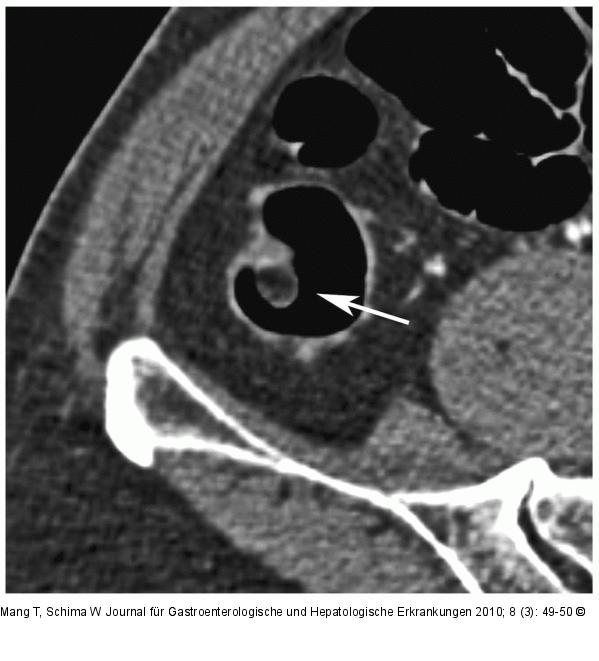

Abbildung 1b: 2D-Bild Das axiale 2D-Bild zeigt die homogene fettäquivalente Dichte (Grauwert entspricht dem subkutanen Fettgewebe) der polypoiden Läsion im Colon ascendens |

Das axiale 2D-Bild zeigt die homogene fettäquivalente Dichte (Grauwert entspricht dem subkutanen Fettgewebe) der polypoiden Läsion im Colon ascendens |